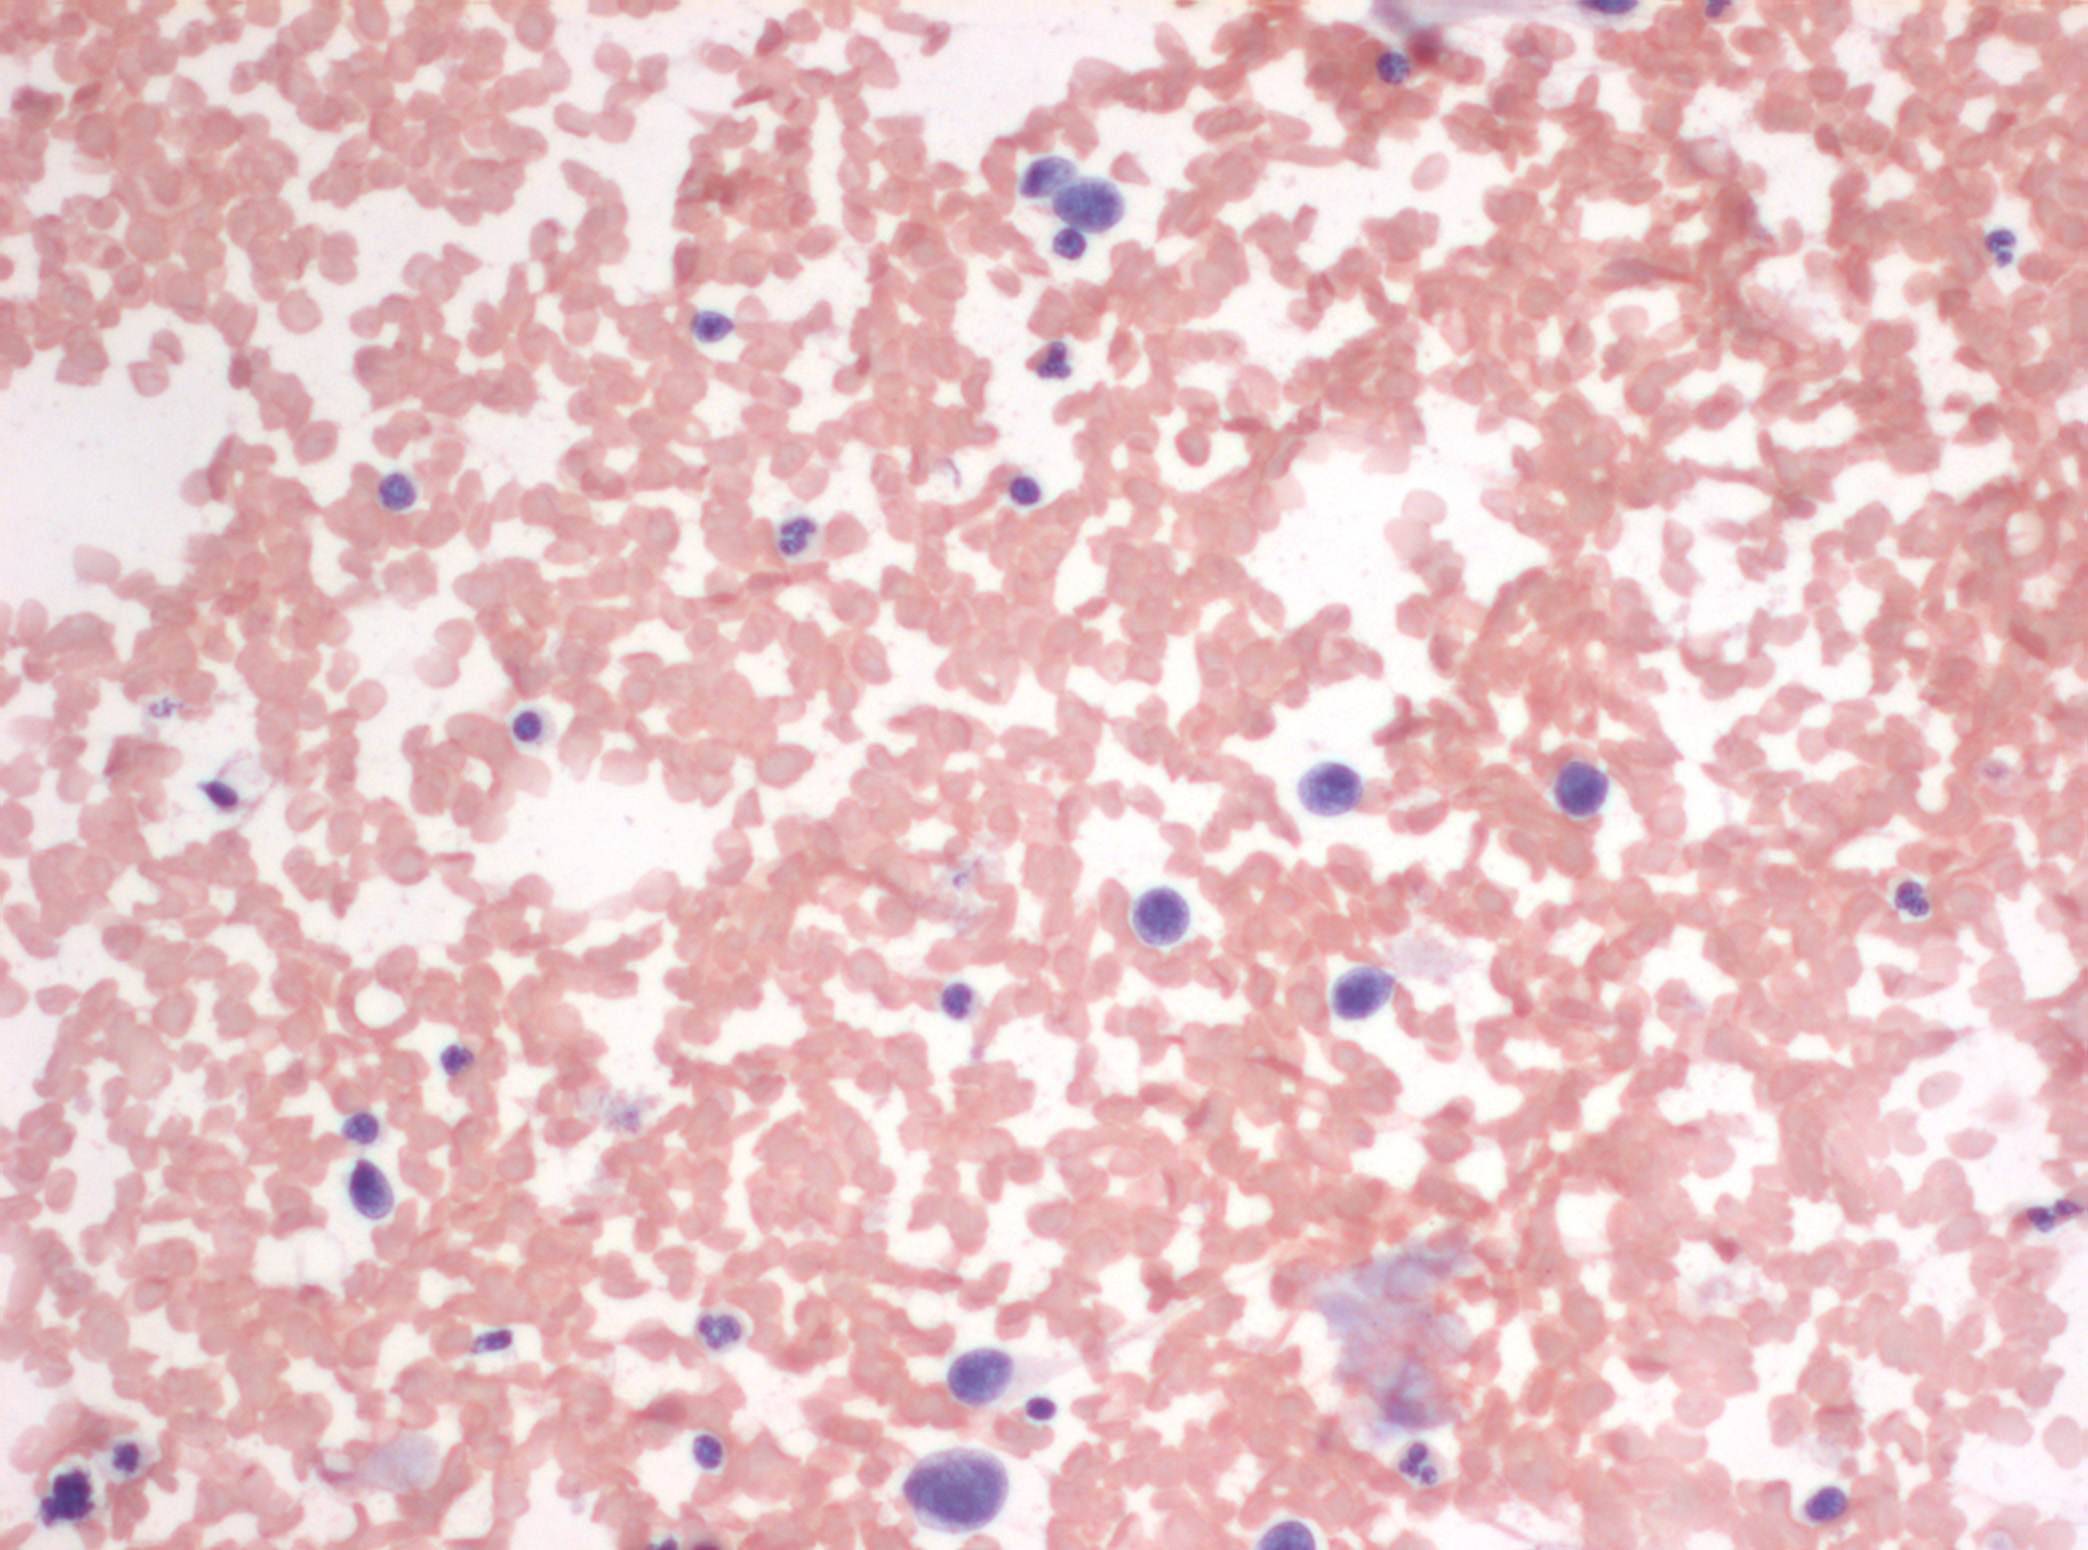

Dr. Alberto Gallardo (patòleg) i Dra. Ferrer (radiòleg).

Clínica Girona

Paciente varón de 54 años con tumoración en unión de cuadrantes superiores de mama izquierda que parece depender del músculo. Se realiza punción con aguja fina.

Se adjunta fotografías de las extensiones, bloque celular y mamografía y ecografía.